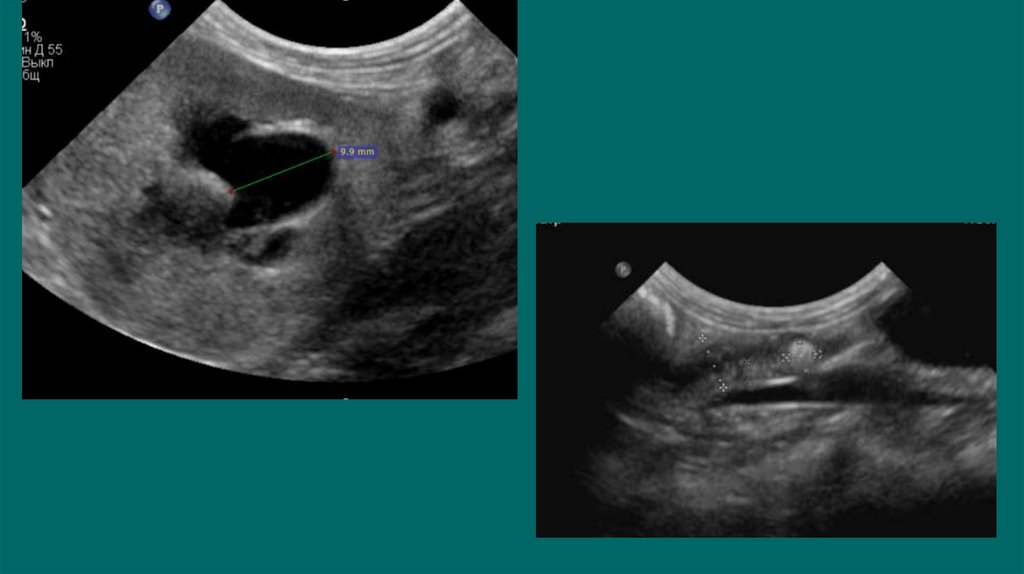

38. УЗИ

Дилатация лоханки более 13 мм - обструкция

При диаметре лоханки более 8мм-высокая

вероятность обструкции

39. Клиническое значение расширения лоханки при УЗИ у кошек/собак

УЗИ 81 собаки и 66 кошек с раширением лоханки.

Было сформировано 6 групп:

1.Клинически нормальная функция почек;

2.Клинически нормальная функция почек при диурезе;

3.Пиелонефриты;

4. Неинфекционной почечной недостаточностью;

5. Обструкция выносящего тракта;

6.Смешанные необструктивные аномалии

Ширина лоханки в 1 группе была ниже, чем в 3-5 группах (среднее значение 2 мм у собак и 1.6 мм у

кошек), но не было

специфичной разницы от группы 2

во 2 группе среднее значение 2.5 у собак и 2.3 у кошек

в 3 группе - 3.6 мм и 4 мм соответственно

в 4 группе - 3.1 мм и 2.8 мм

в 5 группе - 15.1 мм и 6.8 мм

в 6 группе – 3.8 мм и 3.0 мм